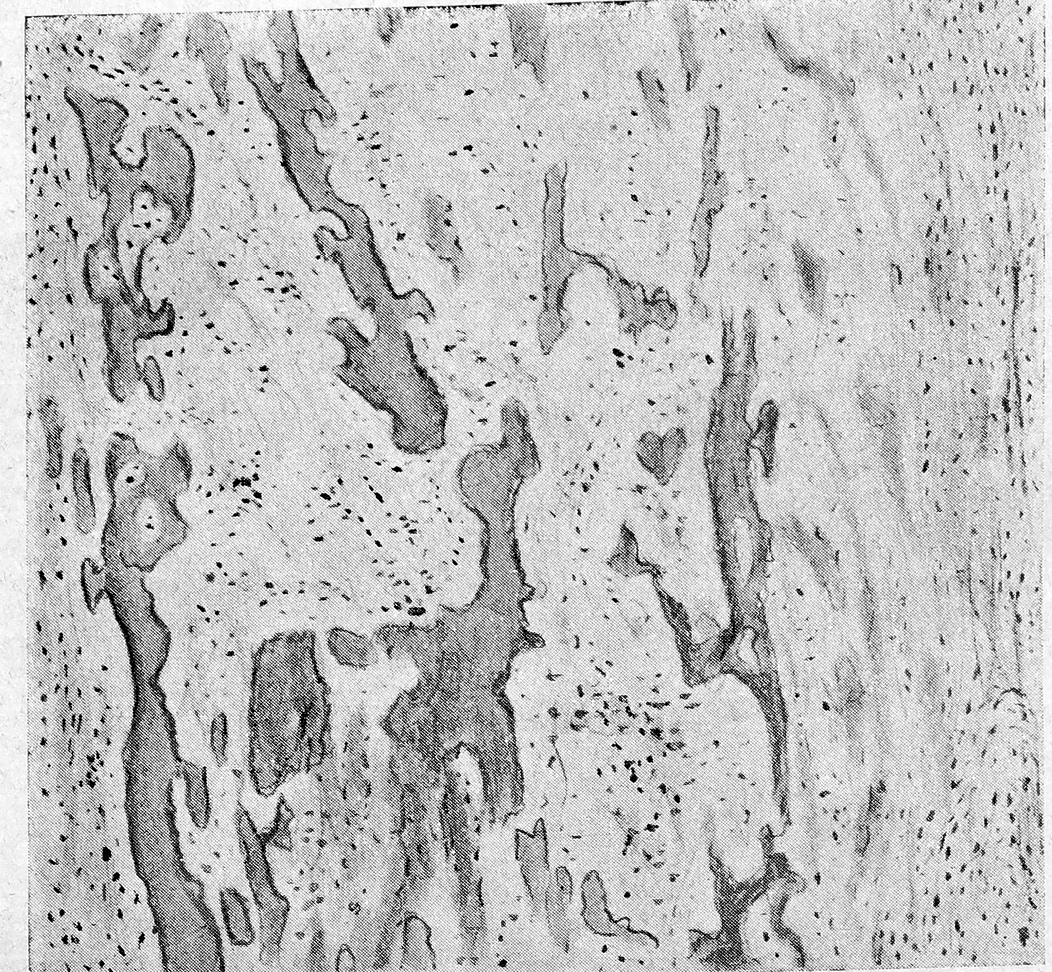

Рис. 6 Участок кости, подвергшейся рассасыванию. Основное вещество кости совершенно утратило нормальную структуру, имеет вид пластинок и полос различной формы с зазубренными краями. Костные тельца незаметны. Ядра не красятся. Между этими участками кости—новообразованная соединительная ткань. Кнутри прилегает плотная волокнистая ткань. Увеличение то же.

Со стороны кости при mucocele наблюдаются явления истончения, рассасывания ее снутри (рис. 6), при новообразовании кости (рис. 7) снаружи—вплоть до образования остеофитов.

Рис. 7. Новообразованная костная ткань. Видны костные перекладины с хорошо заметными костными клетками. По периферии—слой остеобластов. В промежутке между костными перекладинами молодая соединительная ткань с значительным количеством клеточных элементов. Кнаружи от костного вещества соединительная ткань, носящая следы воспаления. В подслизистой ткани, кнаружи от слоя костной ткани (участок взят из носовой стенки Нigmо Новой полости), видны железы Слизистая оболочка покрыта мерцательным цилиндрическим эпителием (эпителий слизистой обол, наружной стенки носовой стенки).